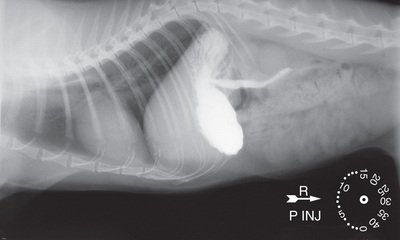

When a special procedure is performed, such as a gastrointestinal contrast study that is part of a series, time elapsed or order taken is also important. In film radiography this designation can be made on the lead tape label. Specialized time clocks can be used in which it is easy to adjust the time lapse (Fig. 15.19). Gravity markers that indicate a patient is standing are also available, although not frequently used.